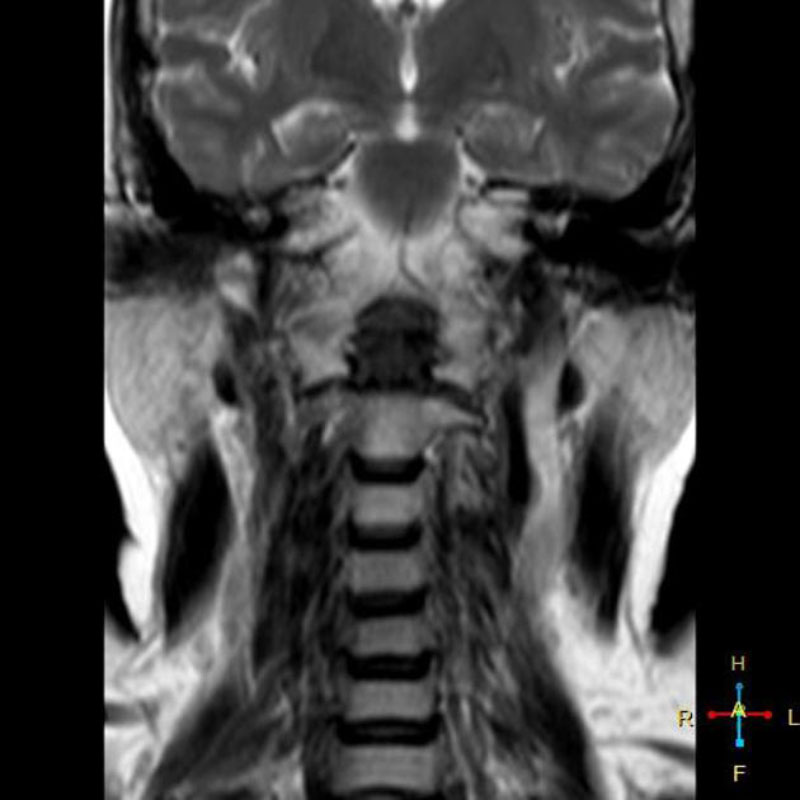

Chụp cộng hưởng từ (MRI) sử dụng từ trường và sóng vô tuyến do máy tính tạo ra để phác họa hình ảnh chi tiết về các cơ quan, mô trong cơ thể. Máy MRI được minh họa như một khối nam châm lớn. Khi người bệnh nằm bên trong, từ trường hoạt động với sóng vô tuyến và các nguyên tử hydro của cơ thể để tạo ra hình ảnh mặt cắt ngang.

Chụp MRI có thể được sử dụng để chẩn đoán các vấn đề về khớp, gồm: